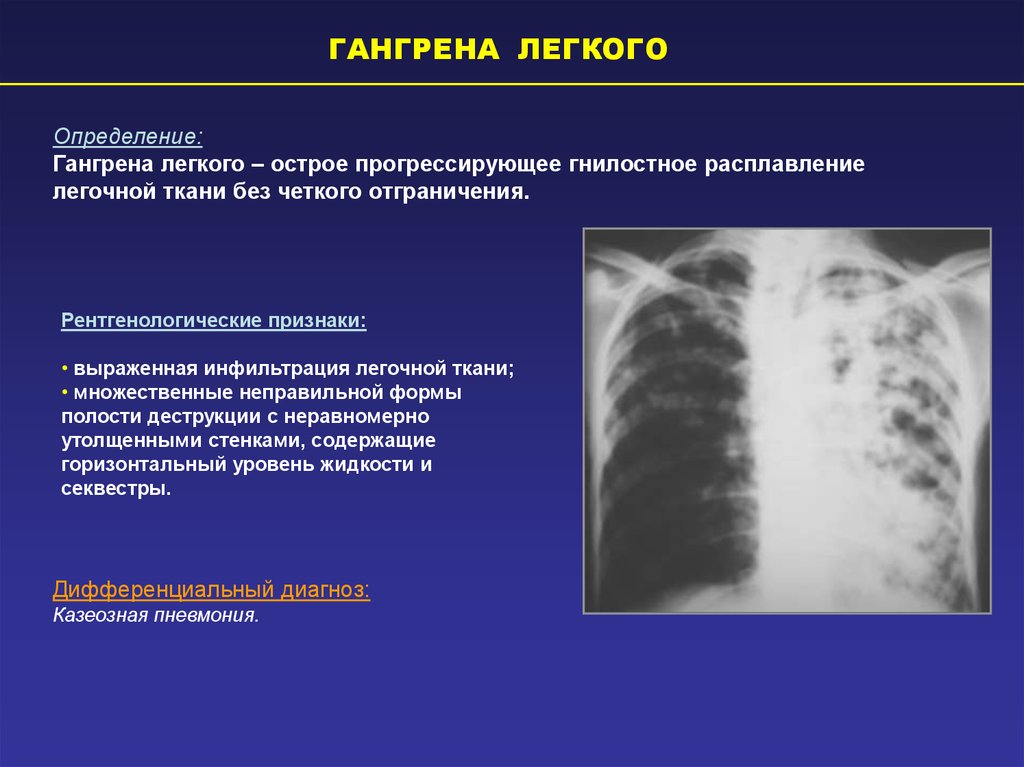

Бактериальная деструкция легких у детей презентация - 88 фото